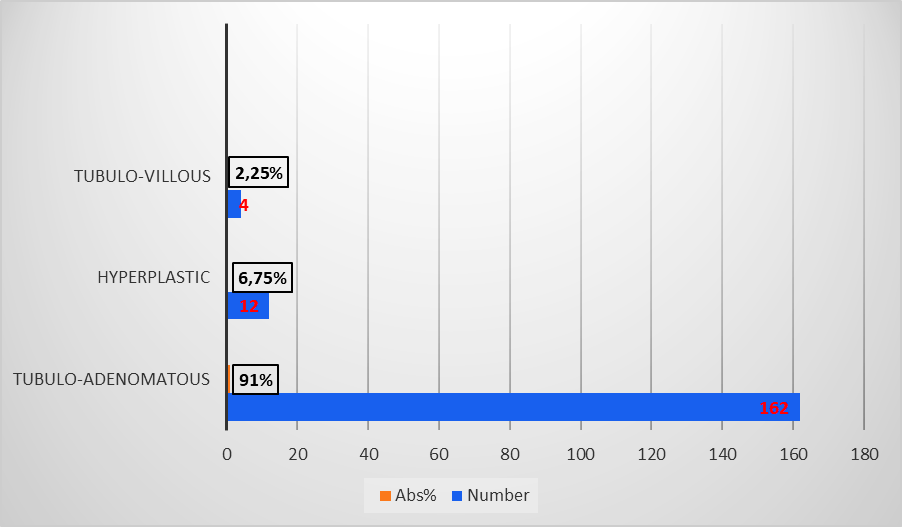

In terms of size, polyps were categorized as follows: under 5 mm (very small polyps), between 5 and 10 mm (small polyps), and over 10 mm (large polyps) [9]. Very small polyps predominated in 86 (48.3%) cases, small polyps in 61 (34.3%), and large polyps represented 17.4% (n = 31). Regarding the histological type, the majority were neoplastic, with tubuloadenomatous polyps predominating (162, 91%), followed by hyperplastic polyps (12, 6.75%) and tubulovillous polyps (4, 2.25%) (Figure 5).

|

Fig. 5 Histological types of premalignant colonic lesions in patients included in the study Note: abs - absolute value in percentage |

The distribution of polyps varied statistically significantly (p = 0.0001) in relation to polyp size and histology. The most frequent, tubuloadenomatous (n = 86), were of very small size, while tubulovillous polyps (n = 4) were of large size, and hyperplastic polyps (n = 12) were equally distributed between small and large sizes (Table 3).